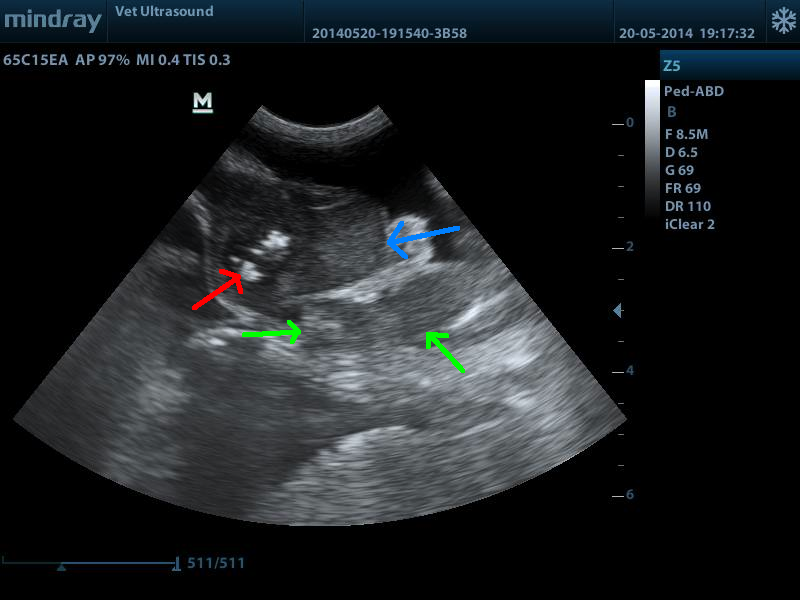

κόκκινο βέλος εντερικό περιεχόμενο, μπλέ βέλος μάζα με απώλεια της χαρακτηριστικής δομής του λεπτού εντέρου., πράσινα βέλη διογκωμένος μεσεντέριος λεμφαδένας.

πάχος την μάζας 0.79 cm, φυσιολογικό πάχος λεπτού εντέρου 0.2 -0.3 cm